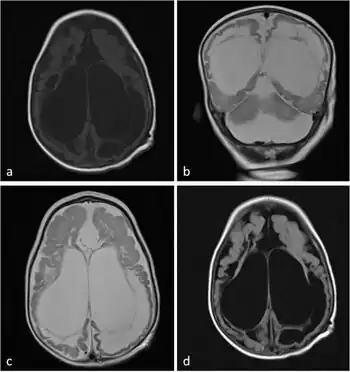

a-d) MRI show ventriculomegaly, cystic encephalomalacia, and extensive subcortical and periventricular white matter loss and hyperintensity in white matter with atrophy.

Diagnosis of molybdenum cofactor deficiency includes early seizures, low blood levels of uric acid, and high levels of sulphite, xanthine, and uric acid in urine. Additionally, the disease produces characteristic MRI images that can aid in diagnosis.[4]